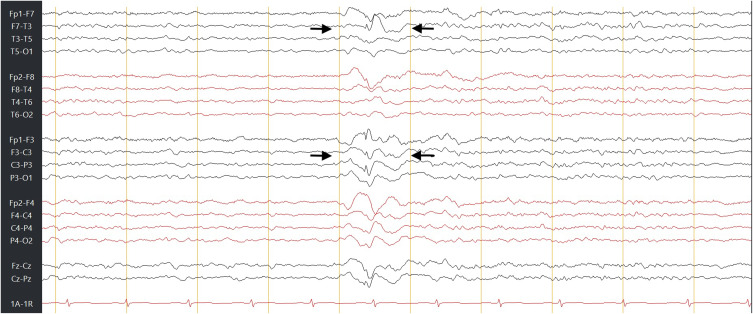

脑脊液(CSF)鼻漏是一种罕见但严重的疾病,最常见于颅底创伤或手术,其表现为癫痫的并发症极为罕见。癫痫管理的重点是癫痫发作控制和预防即时并发症,如癫痫持续状态或跌倒相关损伤。我们描述了一位36岁的男性局灶性癫痫患者,经磁共振成像和β-2转铁蛋白检测证实,他出现了反复发作的脑脊液鼻漏,并伴有暂时性的夜间惊厥和癫痫相关的筛板缺损。我们假设在这些癫痫发作期间反复的轻微颅脑损伤和短暂的颅内压激增导致了颅底缺损。系统地排除了所有其他病因;虽然不能证明明确的因果关系,但强烈的时间关联支持了这一假设。通过内窥镜手术修复成功解决了脑脊液泄漏,并实施了包括改变睡眠安排在内的预防措施。该病例强调了考虑脑脊液渗漏的重要性,癫痫患者出现不明原因的鼻分泌物,强调需要加强癫痫发作管理,及时识别和多学科护理,以防止并发症。

Cerebrospinal fluid (CSF) rhinorrhea is a rare but serious condition that most commonly follows skull-base trauma or surgery, and its manifestation as a complication of epilepsy is exceptionally rare. Epilepsy management focuses on seizure control and prevention of immediate complications, such as status epilepticus or fall-related injuries. We describe a 36-year-old male with focal-onset epilepsy who developed recurrent CSF rhinorrhea temporally associated with nocturnal convulsions and a seizure-related cribriform-plate defect confirmed by magnetic resonance imaging and β-2 transferrin testing. We hypothesize that repeated minor cranial trauma and transient intracranial pressure surges during these seizures precipitated the skull-base defect. All alternative etiologies were systematically excluded; although a definitive causal link cannot be proven, the strong temporal association supports this hypothesis. The CSF leak was successfully addressed through endoscopic surgical repair, and preventive measures, including alterations to sleeping arrangements, were implemented. This case underscores the importance of considering CSF leakage in individuals with epilepsy presenting with unexplained nasal discharge, highlighting the need for enhanced seizure management, prompt recognition, and multidisciplinary care to prevent complications.